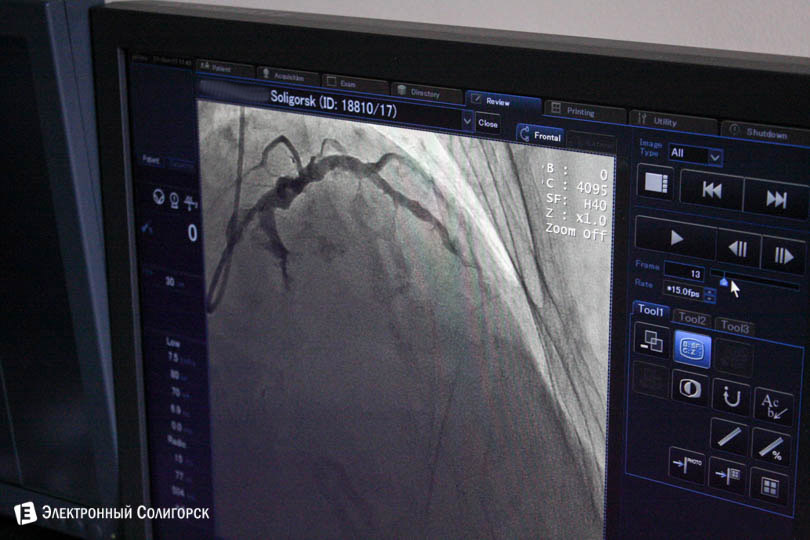

Врачи обезбаливают только место, куда вводят иглу. Чаще всего иглу вводят в запястье или в складку между бедром и пахом. "Пациент всё время в сознании, мы с ним разговариваем. Если кто-то захочет, может на мониторе увидеть, что у него происходит внутри", - рассказывает Александр.